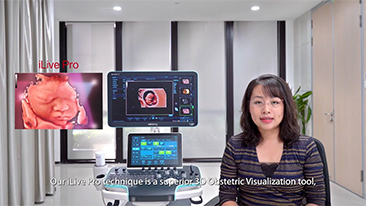

Less Stethoscope, More Ultrasound?

Using ultrasound as part of an optimised OBG workflow can support large patient volumes for women's health screening. For example, central nervous system (CNS) malformations are one of the most common congenital abnormalities. Due to imaging conditions such as poor fetal position, the median sagittal plane (MSP) is particularly difficult to obtain from 2D ultrasound. Therefore, automated detection and measurements can greatly enhance scanning efficiency.